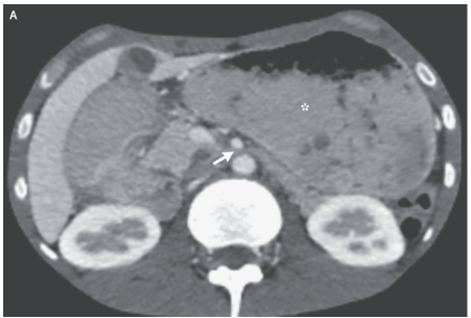

腸間膜脂肪と皮下脂肪はほぼ認めず、胃の拡張と上腸間膜と大動脈に挟まれた十二指腸を認めた(矢印)

嘔吐に関しては結核による全身状態不良による「上腸間膜症候群」と診断された。